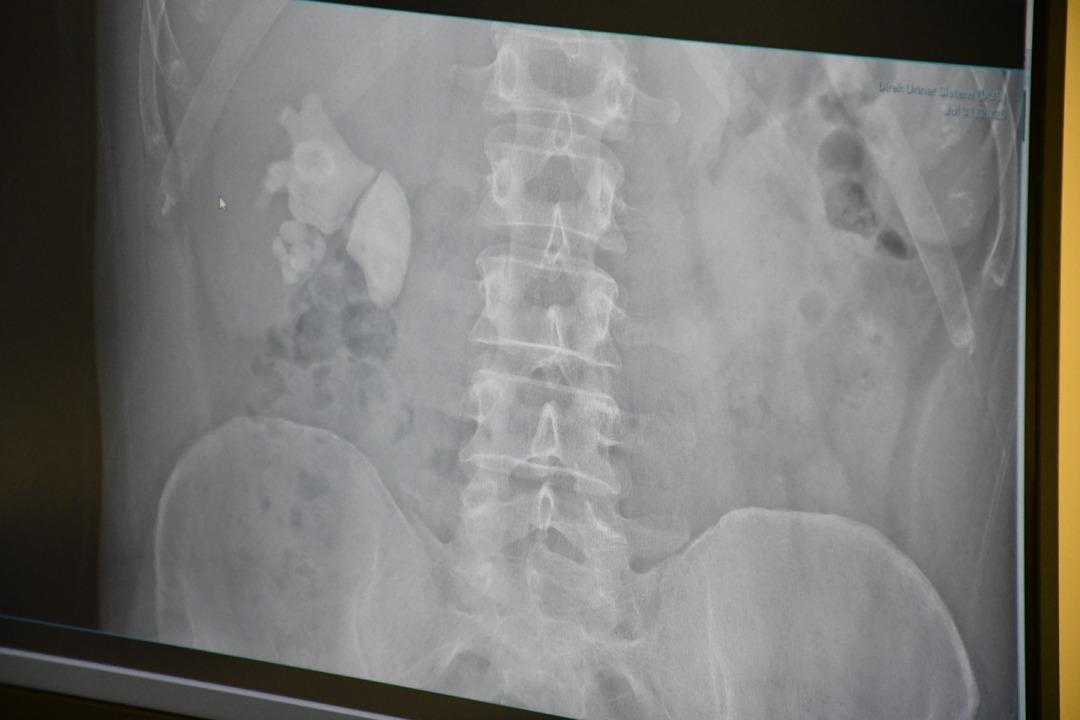

Kendilerini şiddetli böbrek ağrısı ile Yozgat şehrinin hastanesine uygulayan Evran'ın ayrıntılı sınavlarının ardından böbrekte yaklaşık 100 taş tespit edildi.

“Tamam böbrek taş doluydu”

Kamocanoglu, “Sağ böbrek muayenemiz taşlarla doluydu. Hasta hastayla tanıştı ve bu kadar büyük taşlarda büyük bir ameliyat olabilir ve hasta bazı deliklere girdi, ameliyatın sırtını gerçekleştirerek yapılması gerektiğini söyledi. Hasta kabul etti. Hasta ameliyatını Çarşamba günü yaptık.”